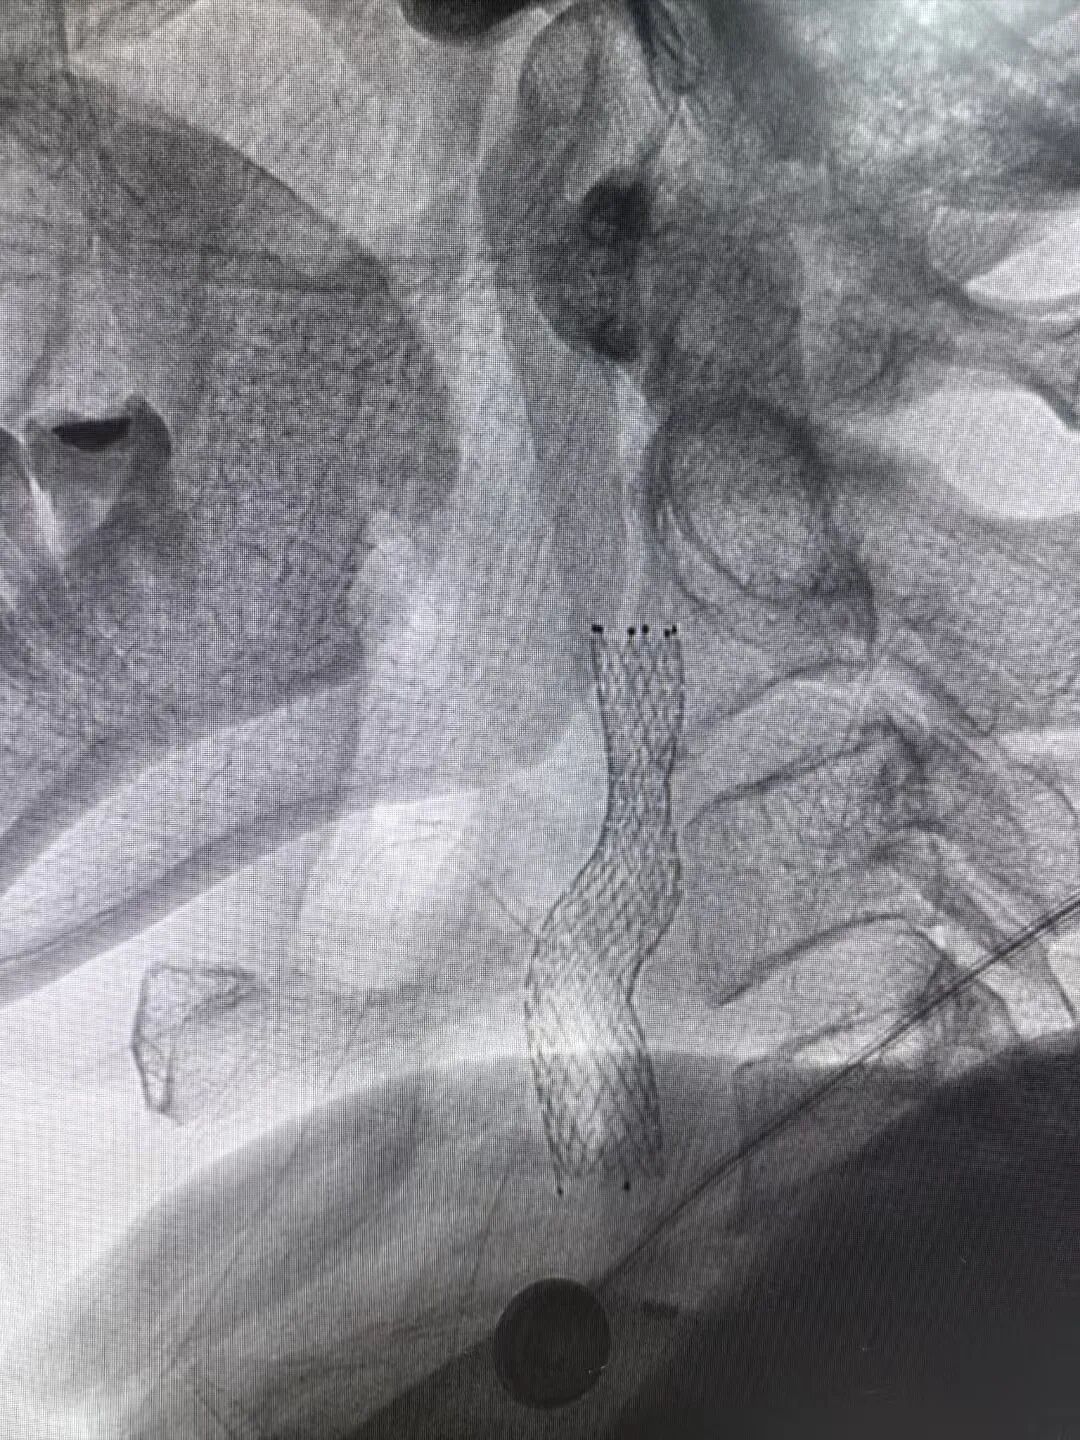

同时,王和平教授紧急到院,带领诊疗团队采用股动脉穿刺微创通路,在DSA引导下精准植入支架,40分钟内解除颈动脉闭塞,造影显示颈动脉血流恢复通畅,术后次日患者即可下床活动。

置入支架术后影像